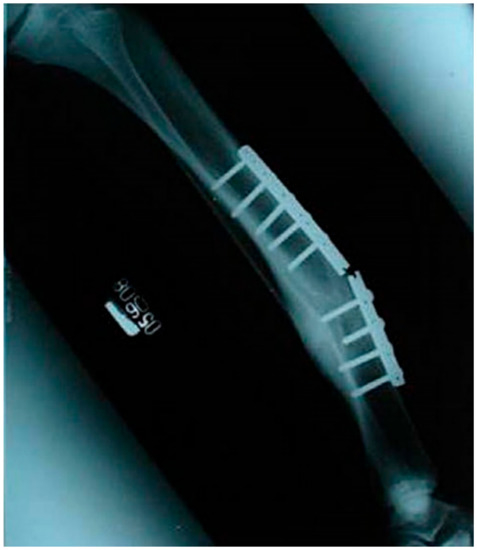

- As described earlier, body implants are subjected to acute and complex loading during service conditions. However, while running or jumping, significantly different loading characteristics are experienced by the medical implants. Therefore, it is necessary to carry out tests under specific loading patterns for a given temporary implant in the actual human body environment.